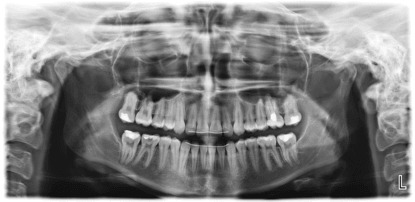

Зъбните снимки, които правим в Медикс, са дигитални. Това означава, че след като бъдат направени, пациентът получава разпечатано копие от специализиран принтер, а цифровият файл се запазва на нашите сървъри. Всеки пациент има своя лична папка, а на всеки дентален медик създаваме личен профил, чрез който получава достъп до папките на своите пациенти. Този подход дава много удобства и предимства както за лекаря, така и за пациента.